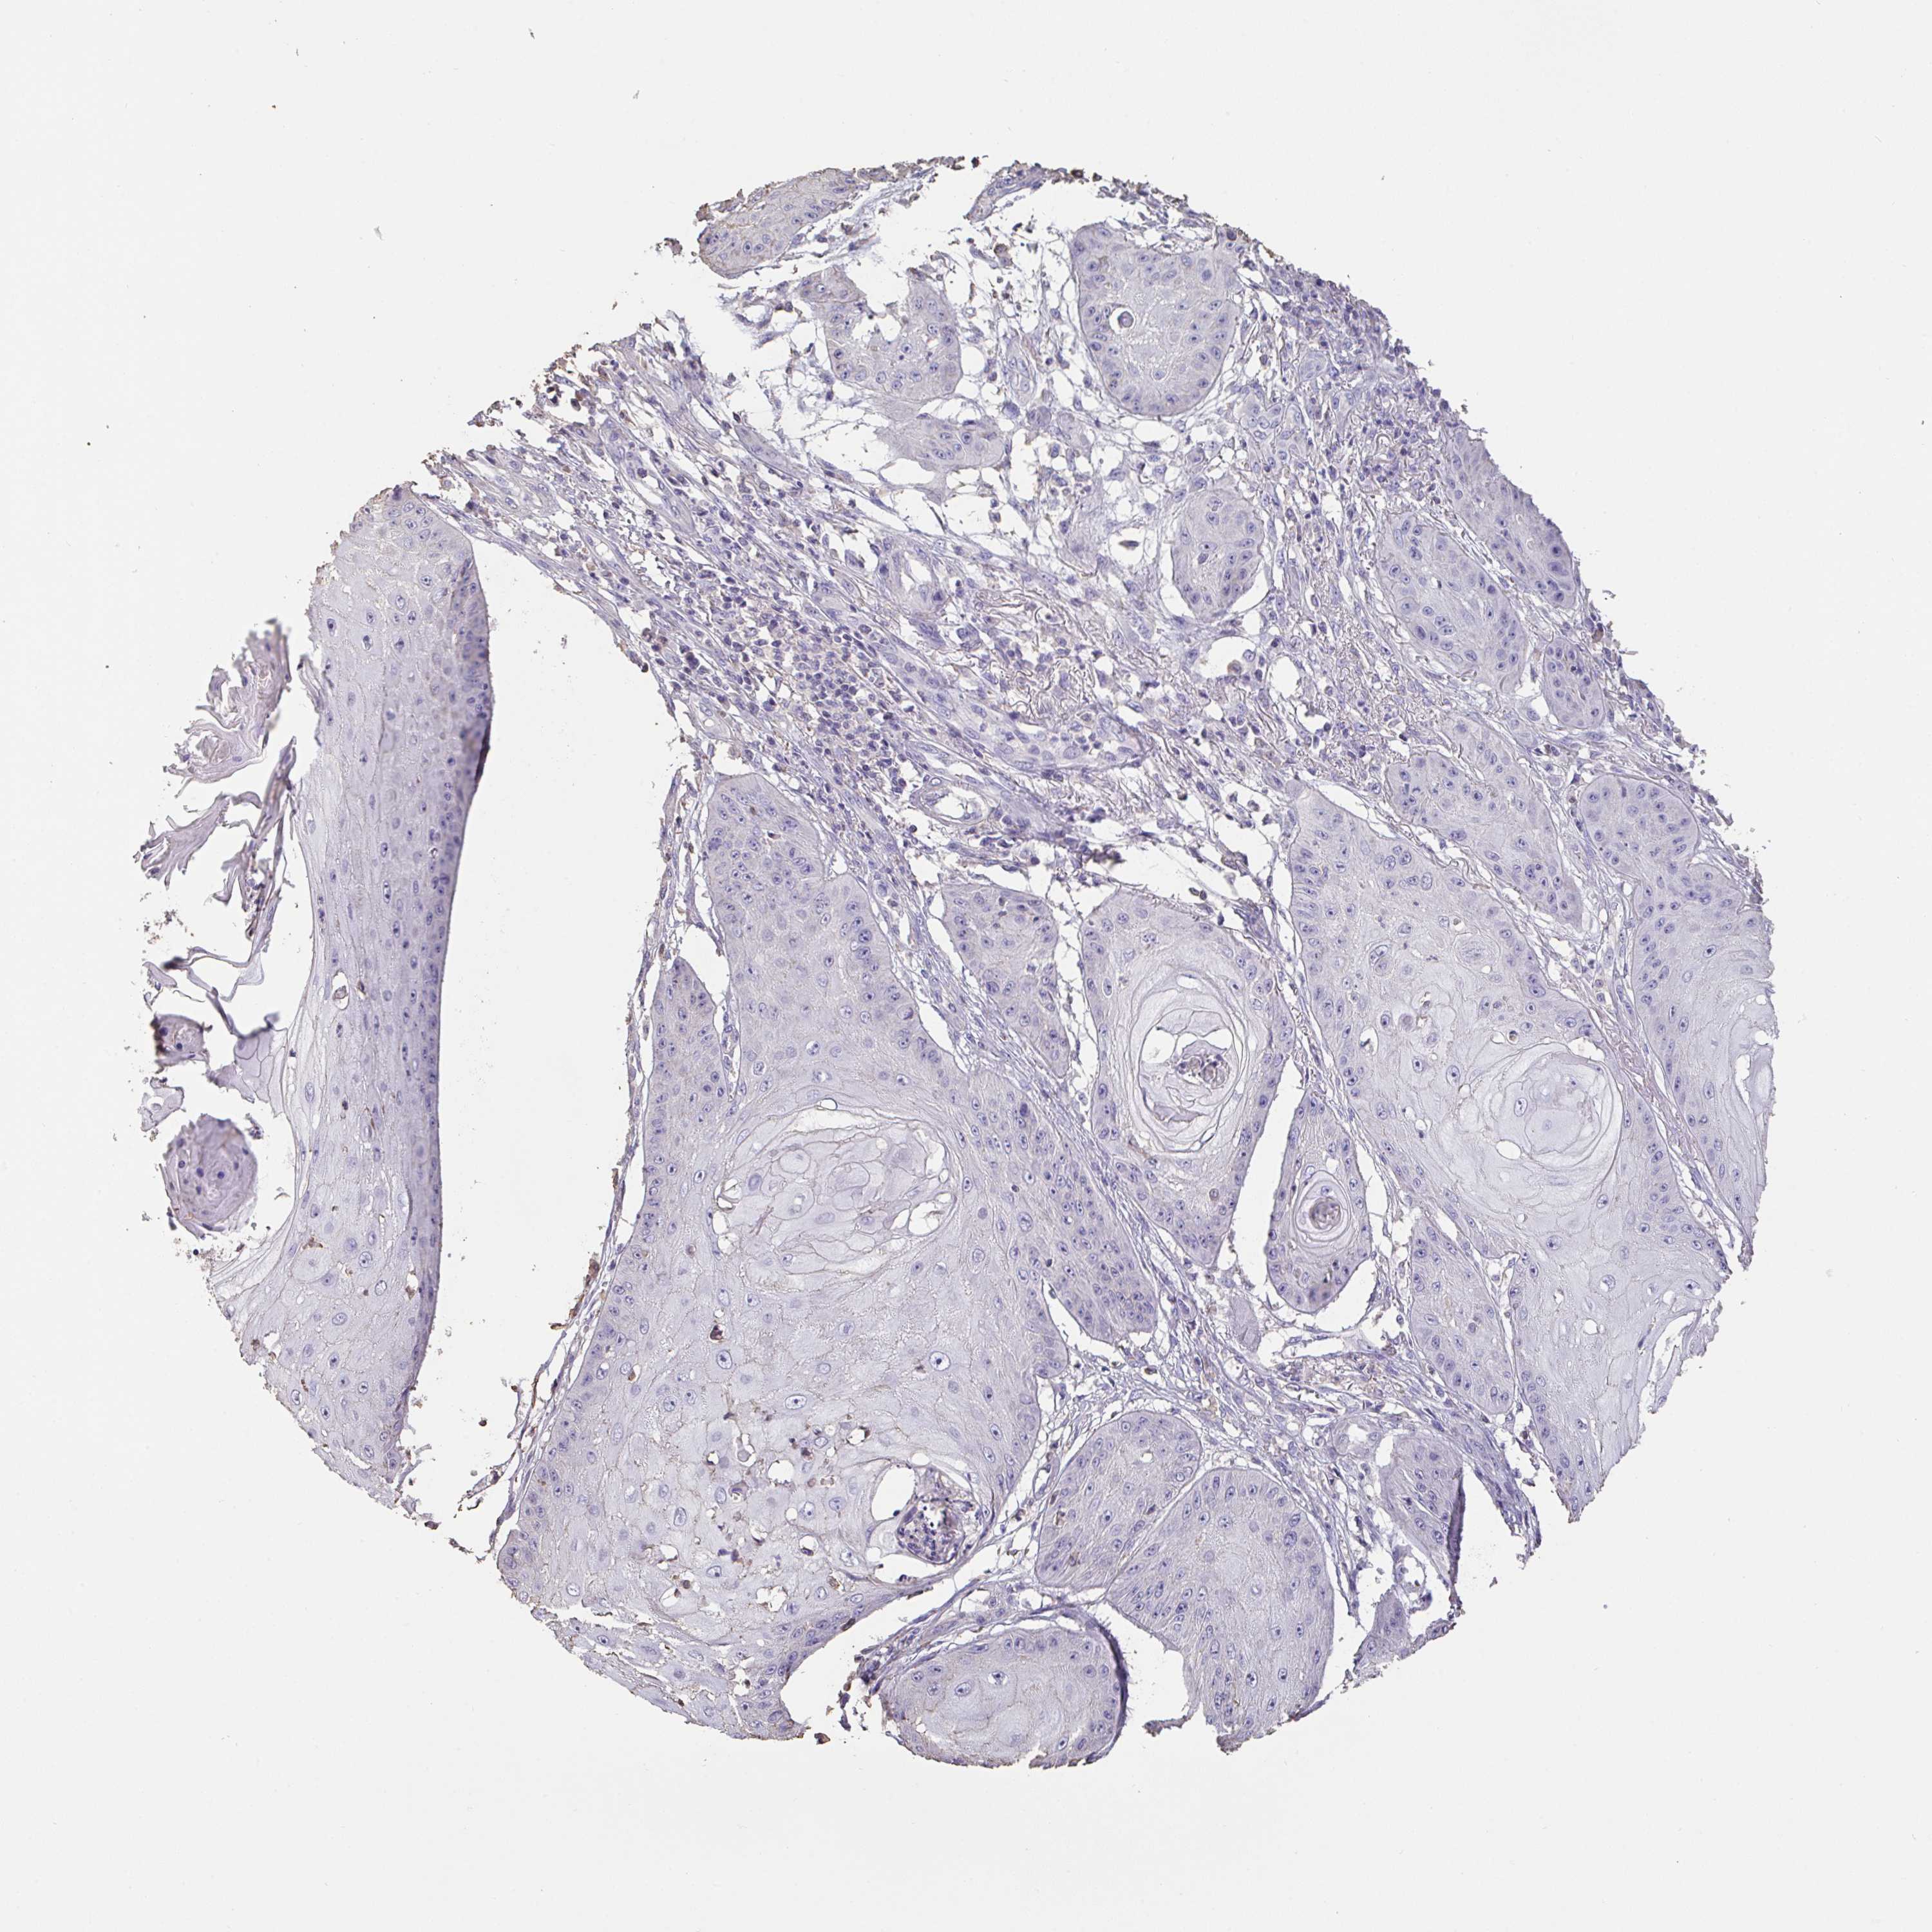

CANCER SKIN CANCER Show tissue menu

Basal cell and squamous cell cancer

SKIN CANCER - Protein expressioni

A mouse-over function shows sample information and annotation data. Click on an image to view it in a full screen mode. Samples can be filtered based on level of antibody staining by selecting one or several of the following categories: high, medium, low and not detected. The assay and annotation is described here.

Each image is clickable and will lead to virtual microscopy that enables deeper exploration of all samples and also displays staining intensity scores, fraction scores and subcellular localization as well as patient and tissue information for each sample.

Antibody HPA056427

Basal cell carcinoma

Squamous cell carcinoma, NOS